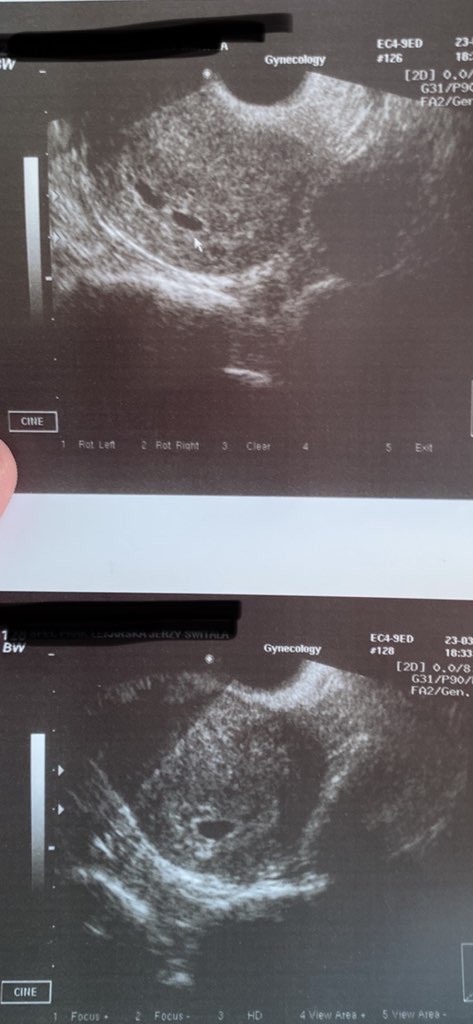

Tak więc ok. Godziny 14 w 34tv+5 na świat przez CC przyszedł Kubuś z waga 2200 (10/10) i Zuzia 2150 (8/10).

Dzieciaki obecnie są w inkubatorach a ja na sali poporodowej. Niby wszytko narazie jest ok, ale martwię się strasznie bo Zuzia leży cały czas z maseczką z tlenem. Lekarz mi.tlaczyl ze Kuba zdążył się przygotować na poród, a Zuzia miała tzw. CC na zimno i dlatego muszą ja bardziej obserwować.